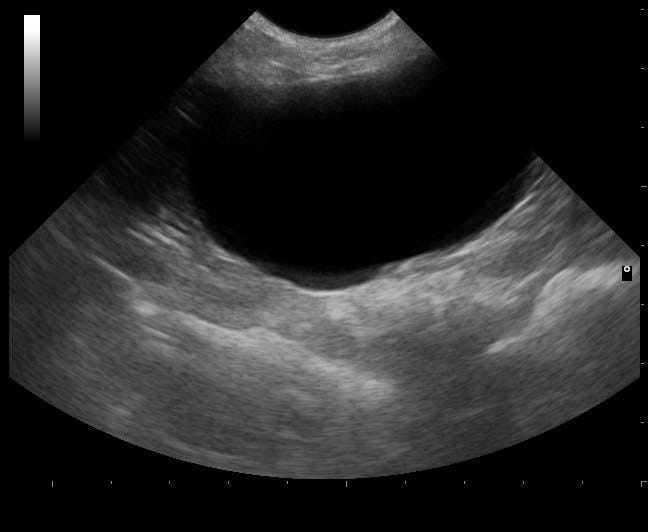

From www.vetlexicon.com

Ultrasonography bladder and urinary tract in Cats (Felis) Vetlexicon What Is The Size Of A Cat's Bladder The urinary system has several important functions. 1 the bladder is located ventral to. a full bladder can cause discomfort and, in severe cases, lead to urinary tract infections or even kidney damage. unlike the canine bladder, the feline bladder remains consistently craniad to the pubis regardless of its degree of distension. The kidneys filter waste from the. What Is The Size Of A Cat's Bladder.

From journals.sagepub.com

Feline abdominal ultrasonography What’s normal? What’s abnormal? Renal What Is The Size Of A Cat's Bladder The goal is to cradle the cat's bladder in your hand, applying the least amount of pressure needed to release the urine. a full bladder can cause discomfort and, in severe cases, lead to urinary tract infections or even kidney damage. 1 the bladder is located ventral to. the size of a cat’s bladder can vary depending on. What Is The Size Of A Cat's Bladder.

of the urinary bladder in a cat Angelo Capasso, Vera What Is The Size Of A Cat's Bladder Sometimes, with a very full. a full bladder can cause discomfort and, in severe cases, lead to urinary tract infections or even kidney damage. the size of a cat’s bladder can vary depending on their age, size, and overall health, but on average, it can hold about 1.5 to 2 fluid. how to express a cat bladder.. What Is The Size Of A Cat's Bladder.